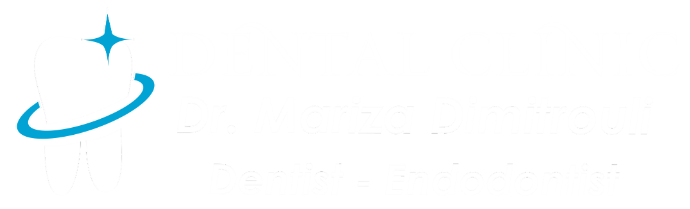

Removal of amalgam (silver) filling

BEFORE

Photo of caries after removal of old black tooth filling